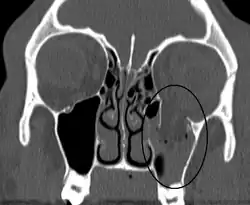

Als Orbitabodenfraktur (Synonyme: Blow-out-Fraktur und Überdruckfraktur) bezeichnet man den (Durch-)Bruch des Augenhöhlenbodens zur Kieferhöhle hin, meist verursacht durch stumpfe Kontusion (z. B. nach Faustschlag oder Tennisballverletzung) und in der Regel verbunden mit der Wahrnehmung von Doppelbildern und deutlichen Störungen der Augenbeweglichkeit. Insbesondere die passive Beweglichkeit ist hierbei eingeschränkt, da Muskel-, Binde- und Haltegewebe häufig in der entstandenen Bruchspalte eingeklemmt sind, oder aber Muskelhämatome für die Bewegungsstörungen verantwortlich sind. Weitere Symptome können ein Anstieg des Augeninnendrucks bei Blick in Richtung der Bewegungseinschränkung sein, ebenso Sensibilitätsstörungen im Bereich der Wangen und Oberlippe, Enophthalmus und Monokelhämatome.

Differenzialdiagnostisch sind die mechanischen Einschränkungen von neurogen bedingten abzugrenzen. Zur Unterscheidung tatsächlicher Augenmuskellähmungen von mechanisch bedingten Bewegungseinschränkungen (Pseudoparesen) verwendet man den so genannten Traktionstest (auch: Pinzettenzugtest), ein Verfahren zur Prüfung der passiven Beweglichkeit des Auges.

Bei reinen Überdruckfrakturen wird eine operative Behandlung mit Rekonstruktionen der Augenhöhle kontrovers diskutiert, da Nutzen und Erfolg umstritten sind. Häufig werden auch spontane Besserungen beobachtet, die vor allem in den ersten vier Wochen nach dem Unfall eintreten können. Aus diesem Grund sollte eine Behandlung und mögliche chirurgische Intervention zuvor genauestens mit allen beteiligten Ärzten (Hals-Nasen-Ohrenarzt, Kieferchirurg, Mund-, Kiefer-, Gesichtschirurg, Augenarzt, Radiologe) erörtert werden. In der Regel wird die Entscheidung zum operativen Vorgehen anhand funktioneller und ästhetischer Einschränkungen (Enophthalmus, Doppelbilder, Einschränkung der Augenbeweglichkeit usw.) getroffen.[1] Eine Unterstützung zur Befunderhebung mittels dreidimensionaler Bildgebung ist heutzutage Standard[2], zunehmend auch die computerassistierte Rekonstruktion.[3]